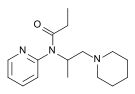

Anilidopiperidines